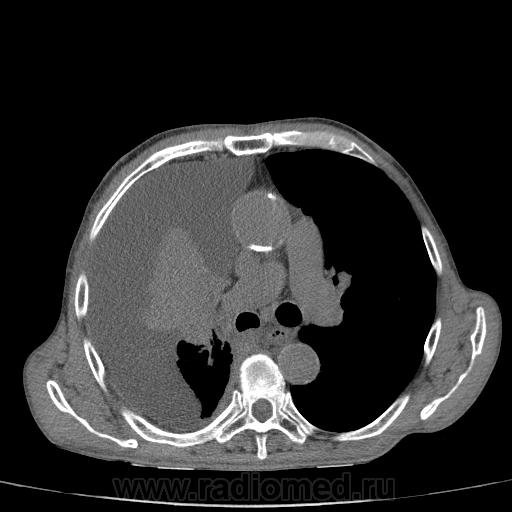

Пожилой мужчина, лечился по н/д правостороннней пневмонии в терап/отделении. Жалобы на одышку, кашель. По результатам Р-контроля после лечения направлен на КТ легких с диагнозом: плеврит справа, распад? В корне правого легкого вижу объёмное образование, с распадом. Смущают размеры плеврита,очень много жидкости, почти до 3 ребра. Анализы крови спокойные- L4,0-6,6, СОЭ 12-16мм. Неужто ТБС, отсев бы был при таком огромном поражении. В посеве мокроты-100% высев клебсиэллы пневмоние. Мокрота на общий анализ в работе-собирает с трудом, изза отсутствия мокроты. Плевральную пункцию еще не проводили. Н азначила бронхоскопию и плеврал пункцию. Как думаете, уважаемые коллеги, это онкопроцесс или тбс распад?

Не смотря дайкомы, только по рентгенограмме, предположил бы центральный рак правого легкого. Потому что большой гидроторакс, без смещения средостения в здоровую сторону, как правило, соответствует раковому ателектазу.

Коллеги, распада там нет, это вас медиастинальное окно подвело. В грудине тоже все в порядке. Да и компрессия позвонка "старая".

Рак.

Небольшое количество увеличенных лимфоузлов, и те - не сказать, чтоб были очень крупными. От эмпиемы до онкологии... Умеренное количество жидкости в перикарде, толщиной слоя до 13-14 мм. При подобной картине не вижу смысла гадать по сжатому лёгкому, пишу так: массивный выпот справа, около 2500 мл, диафрагма оттеснена жидкостью каудально, печень (!!!) смещена каудально и вправо. Легкое справа значительно компрессировано жидкостью, оценка проходимости бронхов и состояния легочной паренхимы (кроме имеющейся эмфиземы) практически невозможна. Необходима пункция плевральной полости справа (цитология, ВК, посев на микрофлору и проч), КТ-контроль после эвакуации жидкости.